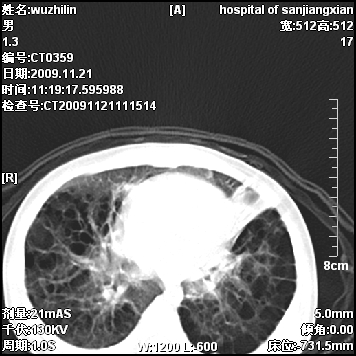

弥漫性薄壁囊腔,胸膜下及肺底部占优势,双上肺磨玻璃密度影,首先考虑特发性肺间质纤维化,其次囊性肺纤维化,肺淋巴管平滑肌瘤病嗜酸性肉芽肿等;要结合临床综合考虑。

两肺布满多个薄壁含气囊腔,以下肺居多,伴磨玻璃样密度影,左侧气胸。两肺发育不全、两肺多发肺囊肿并感染,其次考虑肺囊腺瘤。